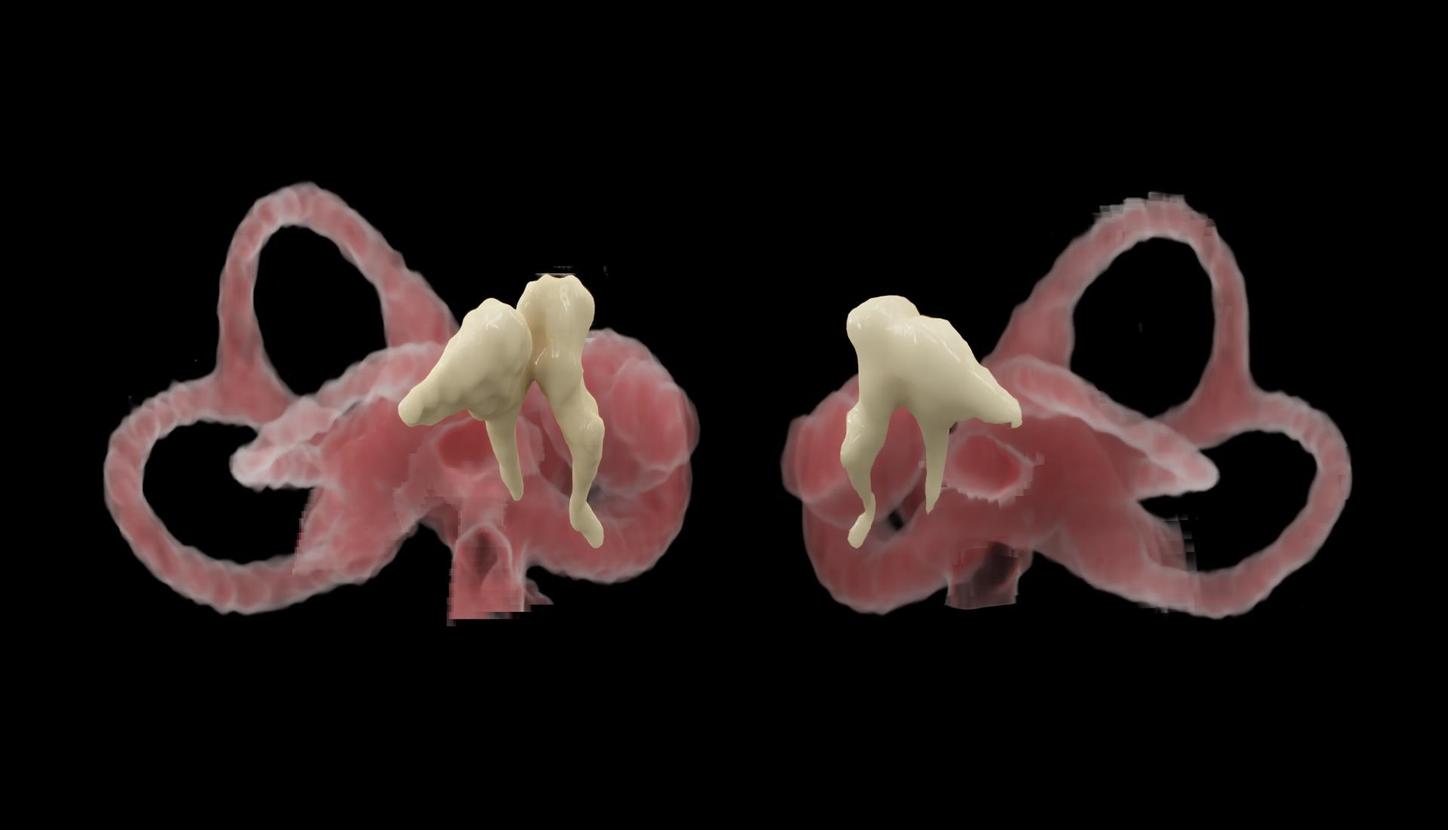

Computed Tomography is moving beyond its traditional diagnostic role to become a key player in early disease detection and therapy planning. This

For research use only. Not for clinical use.